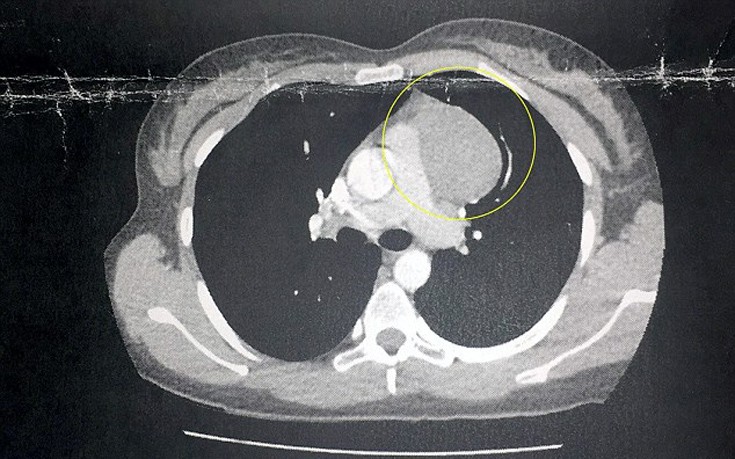

Εκεί με έκπληξη οι ειδικοί διαπίστωσαν πως η νεαρή γυναίκα έπασχε από μία σπάνια μορφή καρκίνου, το «Hodgkin lymphoma», το οποίο προκαλεί τα κόκκινα σημάδια και πρησμένα αγγεία στα πόδια.

Το ευτυχές είναι πως σε αυτή τη περίπτωση η διάγνωση έγινε νωρίς οπότε και ο καρκίνος είναι σε ιάσιμο στάδιο. Δείτε τις χαρακτηριστικές φωτογραφίες και το βίντεο που δημοσίευσε η Daily Mail…